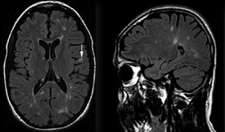

Rapor, sağ böbrek üst pole yerleşmiş bir lezyonu tanımlamaktadır. Bu lezyonun boyutları 35x30 mm olarak belirtilmiş ve düzgün konturlu olduğu ifade edilmiştir. Düzgün konturlu lezyonlar genellikle iyi huylu yapılarla ilişkilendirilir, ancak kesin bir değerlendirme için ek tetkiklere ihtiyaç vardır.

Egzofitk yerleşim, lezyonun böbreğin dışına doğru büyüdüğünü göstermektedir. Bu durum, lezyonun doğasına dair ipuçları verebilir. Solit lezyonlar, genellikle tek başına bulunan ve çevresinde yayılım göstermeyen oluşumlardır. Ancak, bu tür lezyonların değerlendirilmesinde görüntüleme yöntemlerinin önemi büyüktür.

Rapor, kontrastlı tüm batın BT (Bilgisayarlı Tomografi) önerilmektedir. Bu tetkik, lezyonun özelliklerini daha ayrıntılı incelemek, çevresindeki dokularla olan ilişkisini değerlendirmek ve olası metastaz veya yayılım durumunu gözlemlemek açısından büyük önem taşımaktadır.